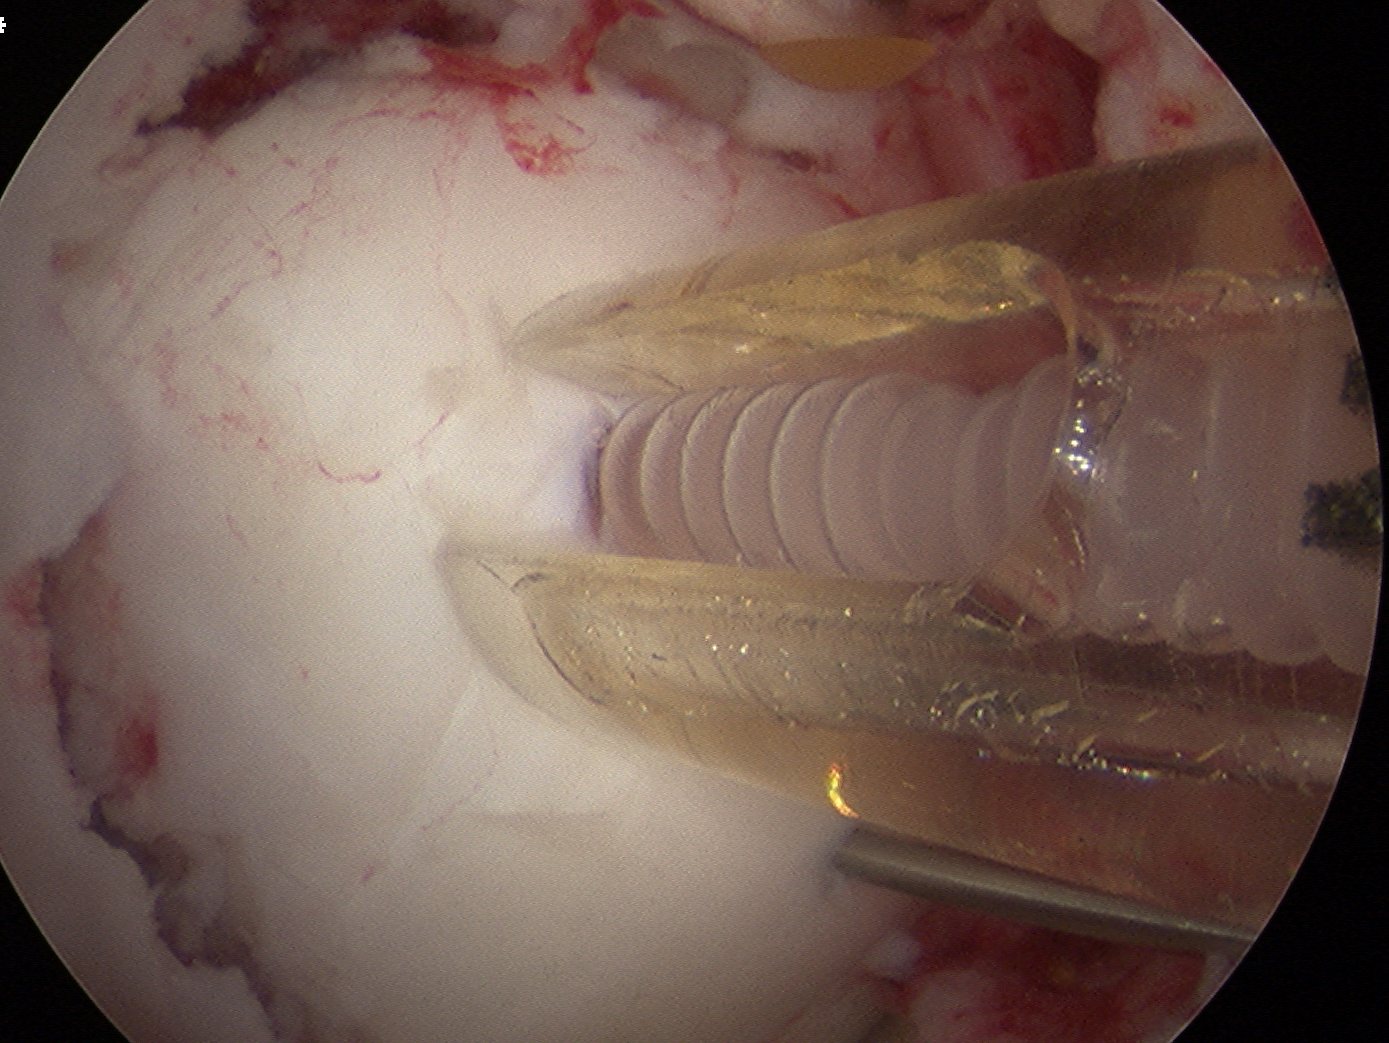

ORIF

In this case, 2 x Arthrex bioabsorble screws used

- drill and tap over wire

- remove wire

- insert screw and bury head